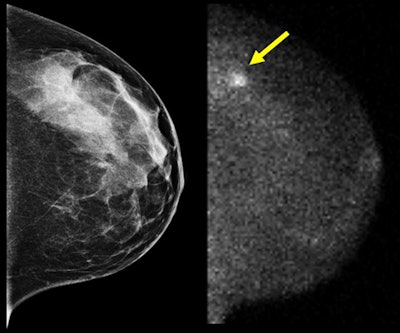

A 45-year-old woman with elevated risk for breast cancer due to breast density underwent digital screening mammogram (left)

and screening MBI (right) as part of a clinical trial.

A biopsy from the area of suspicious technetium-99m (Tc-99m) sestamibi uptake (arrow) indicated the presence of a large lobular

carcinoma. All images courtesy of Carrie Hruska, PhD.